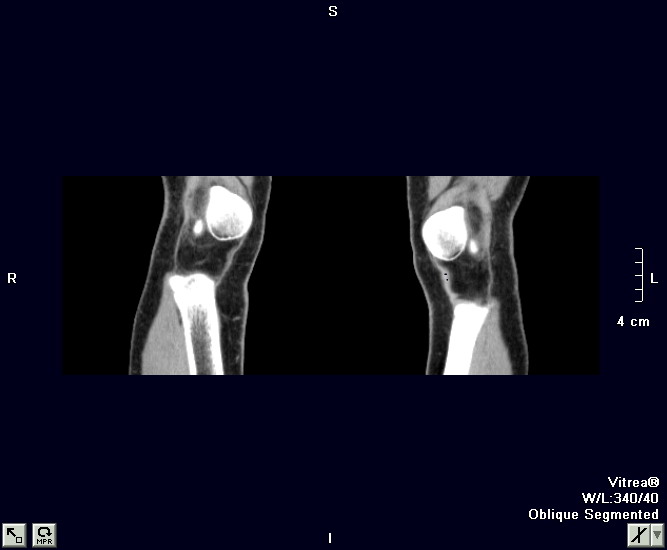

以下是引用zxl51642在2010-2-20 14:49:00的发言:[br]1)左胫骨近端干骺端外生骨疣,同意。[br]2)右胫骨纤维骨皮质缺损?不同意。[br]fcd无软组织肿块,是否可考虑软组织病变如骨膜软骨瘤、骨膜硬纤维瘤、神经纤维瘤之类的病变,给平片和ct轴位像。

以下是引用zxl51642在2010-2-20 14:49:00的发言:[br]1)左胫骨近端干骺端外生骨疣,同意。[br]2)右胫骨纤维骨皮质缺损?不同意。[br]fcd无软组织肿块,是否可考虑软组织病变如骨膜软骨瘤、骨膜硬纤维瘤、神经纤维瘤之类的病变,给平片和ct轴位像。